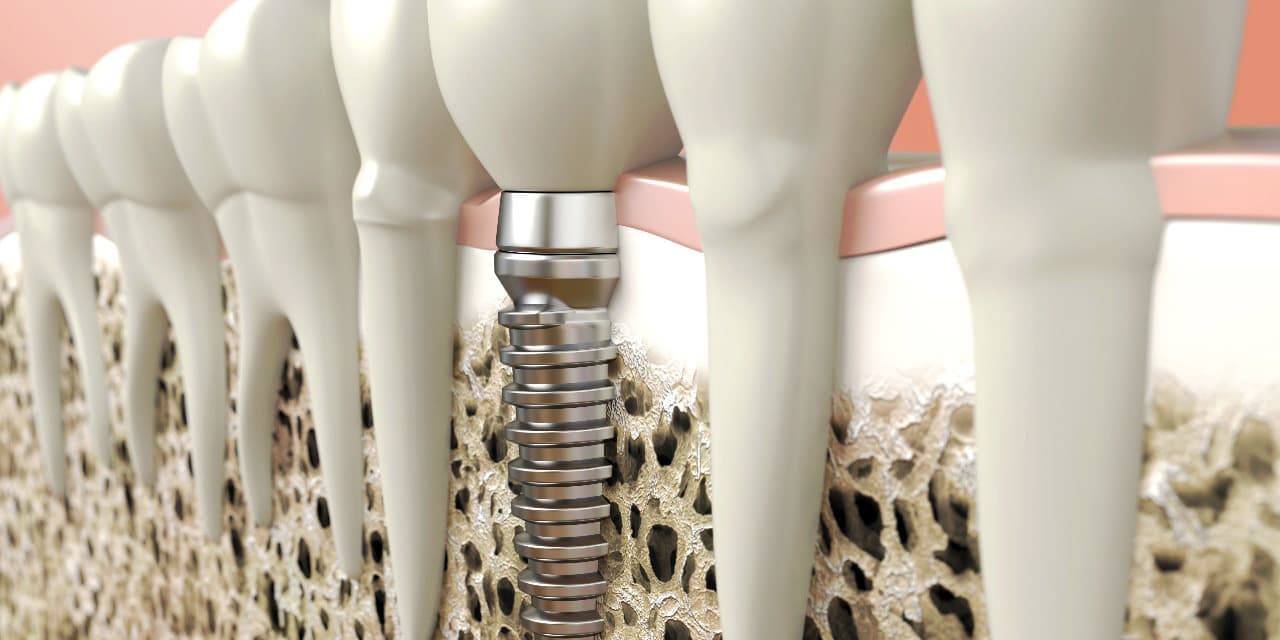

CTによる詳細な現状把握

レントゲンでは把握できないことまでCTでは確認することが出来ます。

身体を断面や立体図として見ることができ、骨はもちろんの事、神経や血管に至るまで確認することができます。

そのデータを元に、どのような角度、どのような深さでインプラントを打ち込むかなど、的確な治療計画を立てることができます。